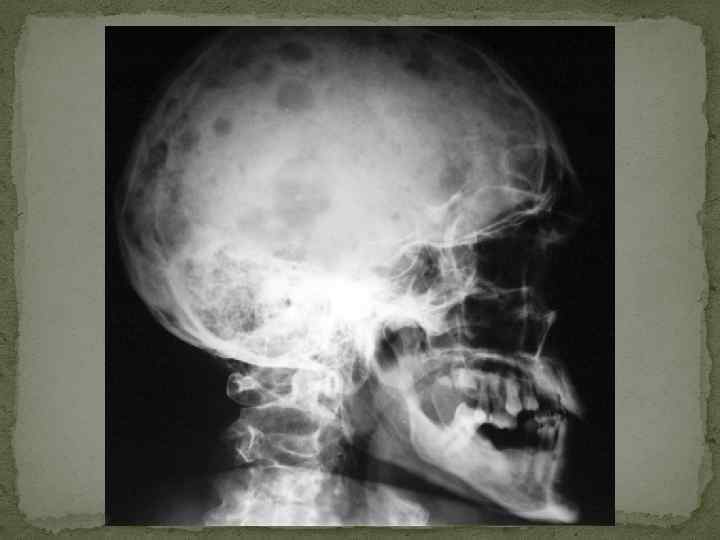

Клиника множественной миеломы (1). 1. Костномозговой синдром. Пролиферирующие в костном мозге миеломные клетки приводят к разрушению костного вещества и деструкции костей. Рентгенологически более чем у 80% больных выявляется генерализованный остеопороз с участками остеолиза, патологические переломы костей. Наиболее часто поражаются кости свода черепа, таза, ребер, позвоночника, реже – проксимальные отделы трубчатых костей (плечо, бедро). Особо следует подчеркнуть, что у 1030% больных возможно развитие компрессия спинного мозга или поражение конского хвоста. Это требует быстрой диагностики и лечения (при ламинэктомии в течение первых 24 часов от развития данного осложнения полное восстановление функции спинного мозга отмечается у 50%, частичное – у 30% больных; операция, выполненная позднее, сопровождается резким ухудшением результатов). Трепанобиопсия в 90 -95% случаев выявляет плазмоклеточную пролиферацию с вытеснением нормальных миелоидных элементов.

Дообследование при миеломе Рентгенография черепа – симптом пробойника (штампованные дефекты, «кучерявый череп» , «череп в виде шляпы, изъеденной молью» ) – не является основанием для диагноза, а лишь подтверждает его. Исследование мочи – диагностически значим уровень белка Бенс-Джонса более 50 мг/л. Необходимо помнить, что в связи с опасностью развития необратимой почечной недостаточности (образование нерастворимого комплекса парапротеин + йодсодержащее рентгенконтрастное вещество) при миеломе Бенс. Джонса категорически противопоказано проведение внутривенной урографии.